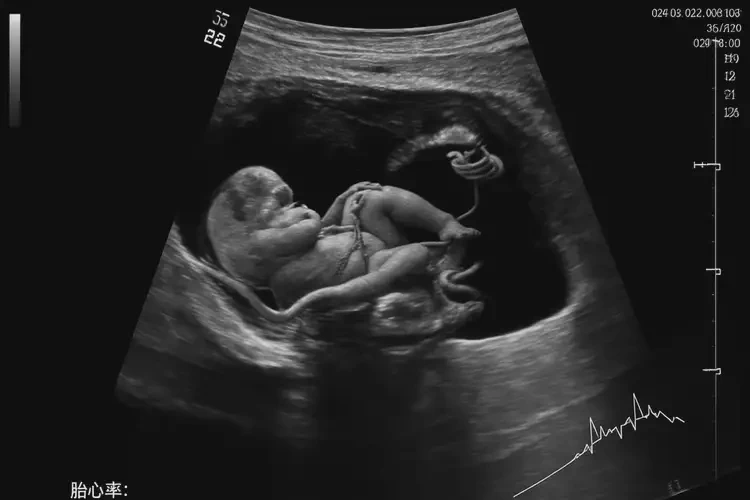

孕32周3天胎心率100還能保住嗎(圖1)